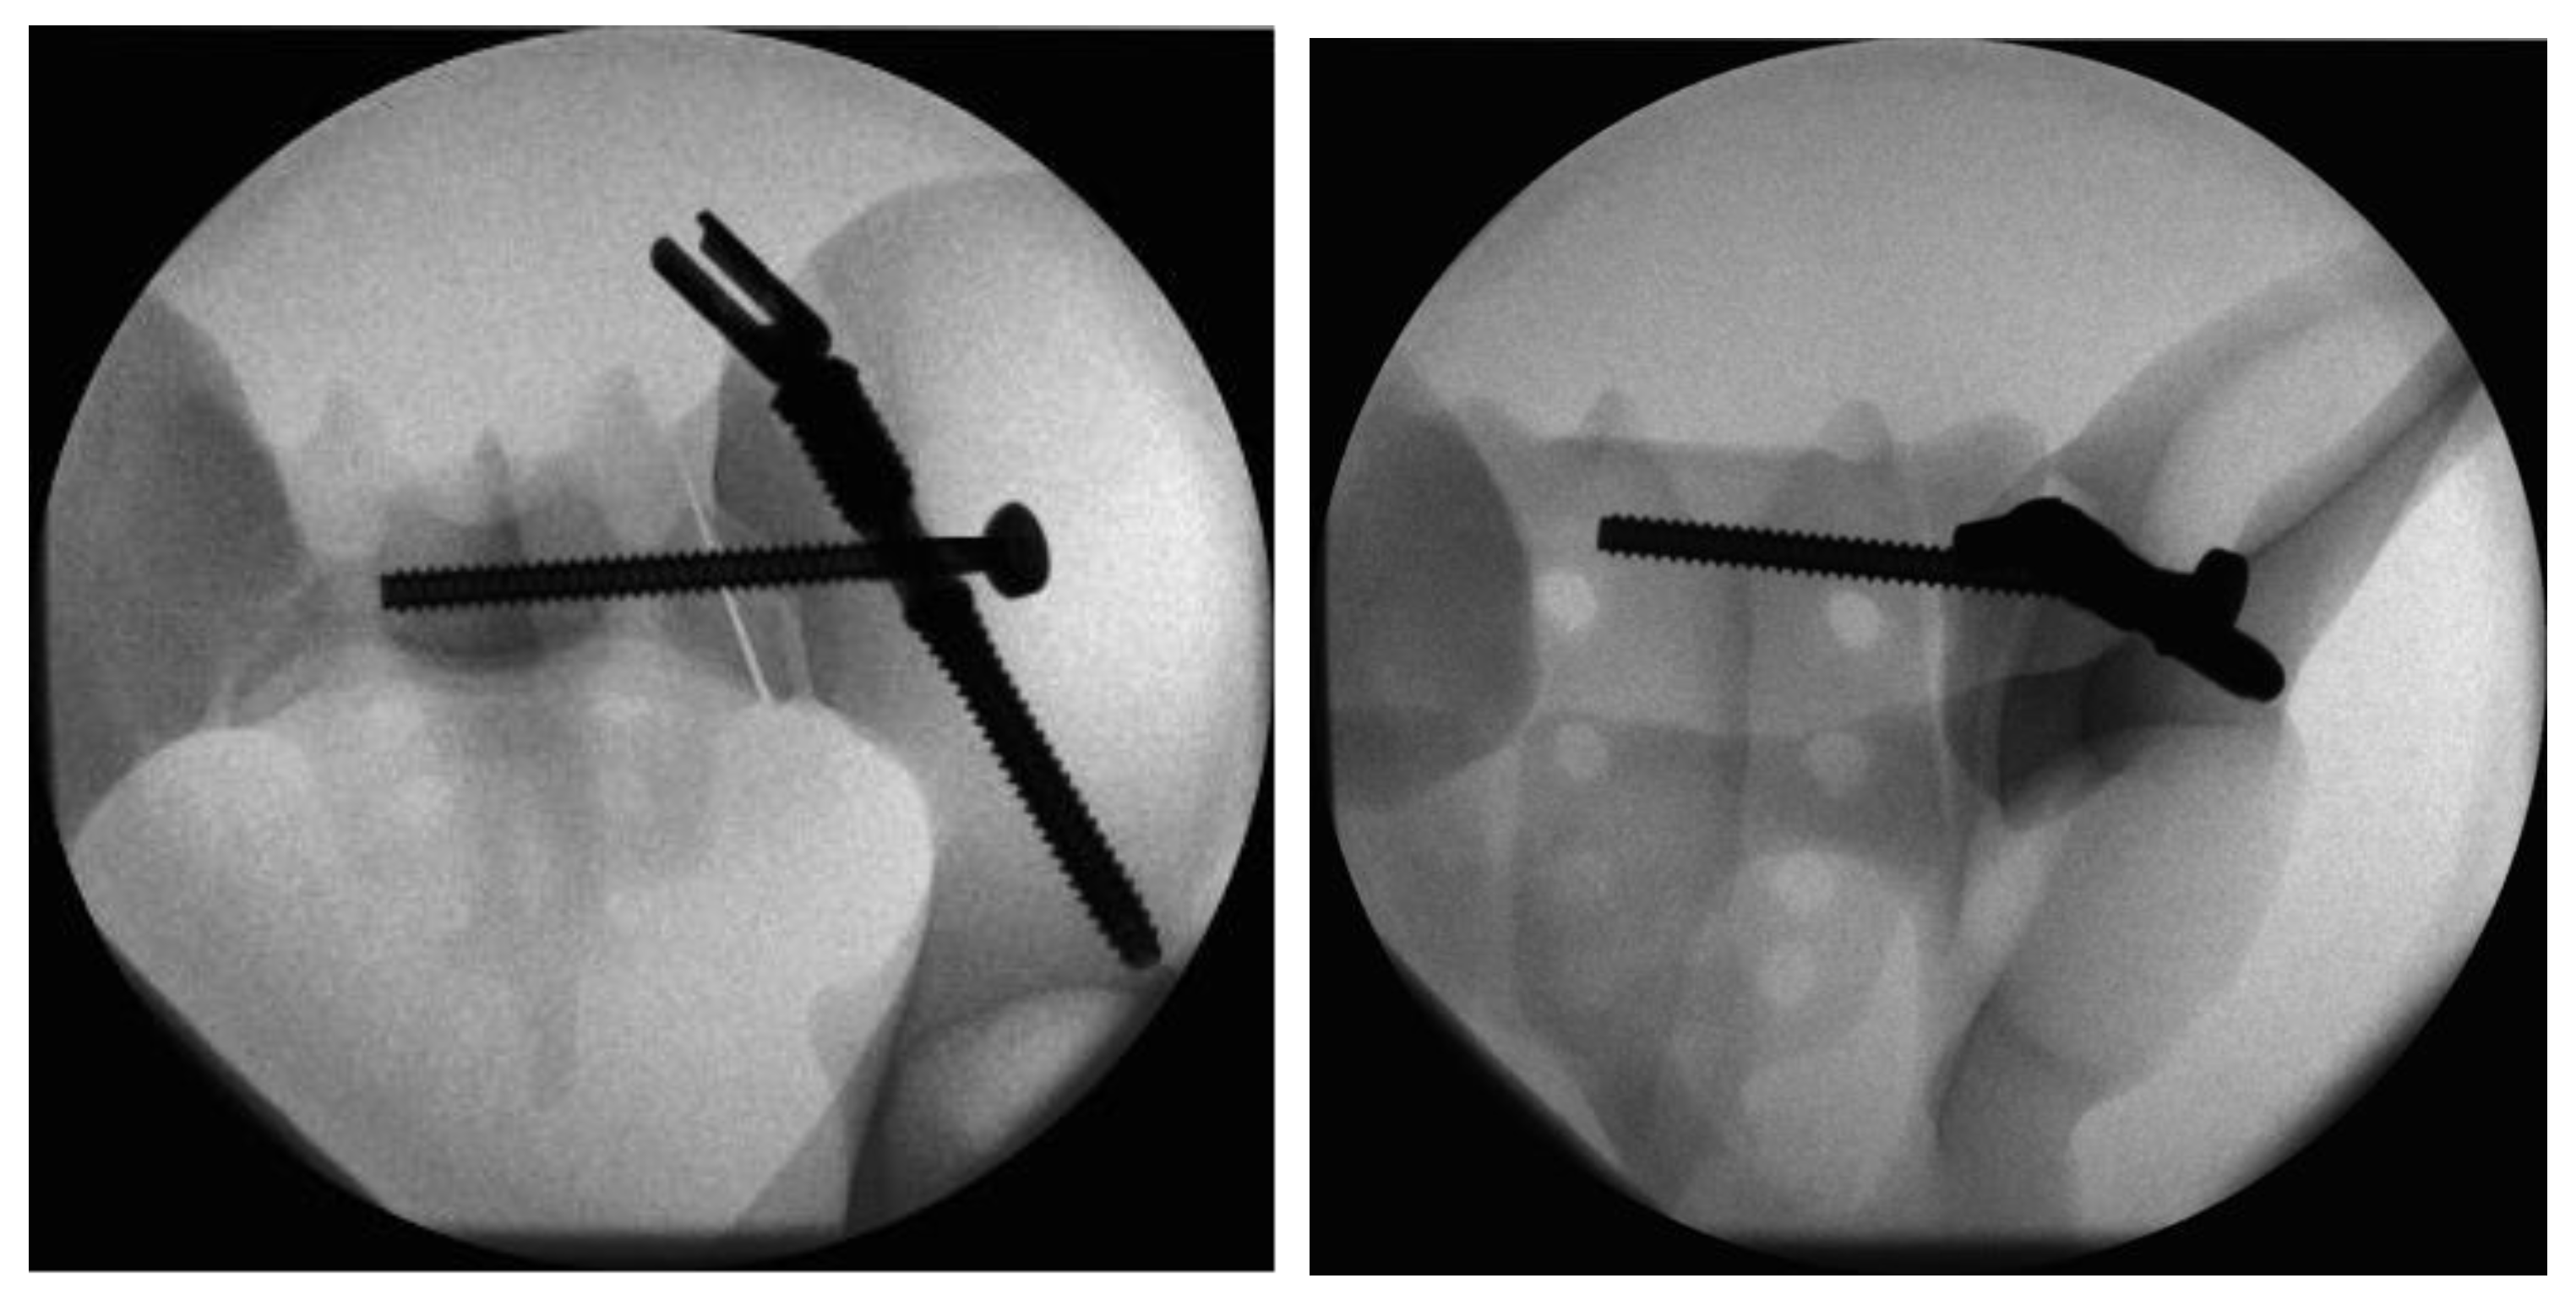

2.3. Fracture Model and Instrumentation

2.4. Biomechanical Testing